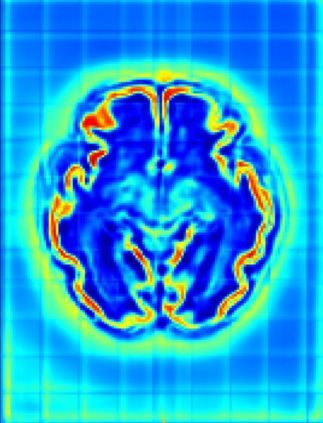

Fetal cortical plate segmentation is essential in quantitative analysis of fetal brain maturation and cortical folding. Manual segmentation of the cortical plate, or manual refinement of automatic segmentations is tedious and time-consuming. Automatic segmentation of the cortical plate, on the other hand, is challenged by the relatively low resolution of the reconstructed fetal brain MRI scans compared to the thin structure of the cortical plate, partial voluming, and the wide range of variations in the morphology of the cortical plate as the brain matures during gestation. To reduce the burden of manual refinement of segmentations, we have developed a new and powerful deep learning segmentation method. Our method exploits new deep attentive modules with mixed kernel convolutions within a fully convolutional neural network architecture that utilizes deep supervision and residual connections. We evaluated our method quantitatively based on several performance measures and expert evaluations. Results show that our method outperforms several state-of-the-art deep models for segmentation, as well as a state-of-the-art multi-atlas segmentation technique. We achieved average Dice similarity coefficient of 0.87, average Hausdorff distance of 0.96 mm, and average symmetric surface difference of 0.28 mm on reconstructed fetal brain MRI scans of fetuses scanned in the gestational age range of 16 to 39 weeks. With a computation time of less than 1 minute per fetal brain, our method can facilitate and accelerate large-scale studies on normal and altered fetal brain cortical maturation and folding.